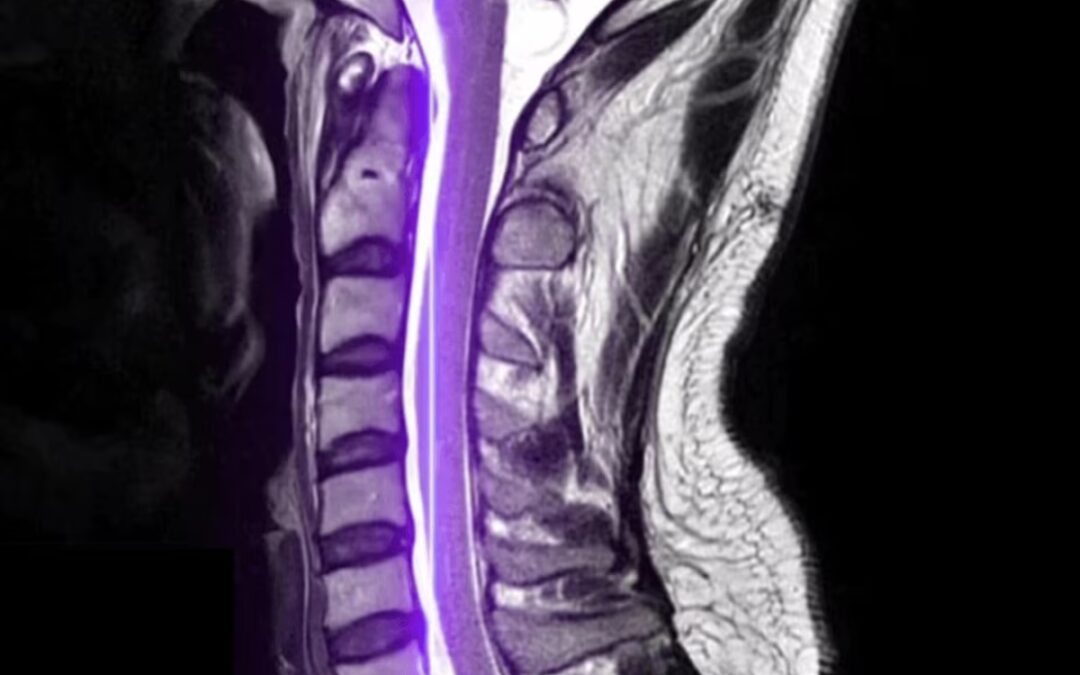

When your doctor needs a clear, detailed look inside your body, a CT (Computed Tomography) scan is often the go-to imaging tool. Also called a CAT scan, this advanced technology combines X-rays and computer processing to create cross-sectional images (or “slices”) of your bones, organs, blood vessels, and soft tissues, giving physicians a much clearer picture than a standard X-ray.

– Assess bone and joint problems (fractures, arthritis, spinal issues)